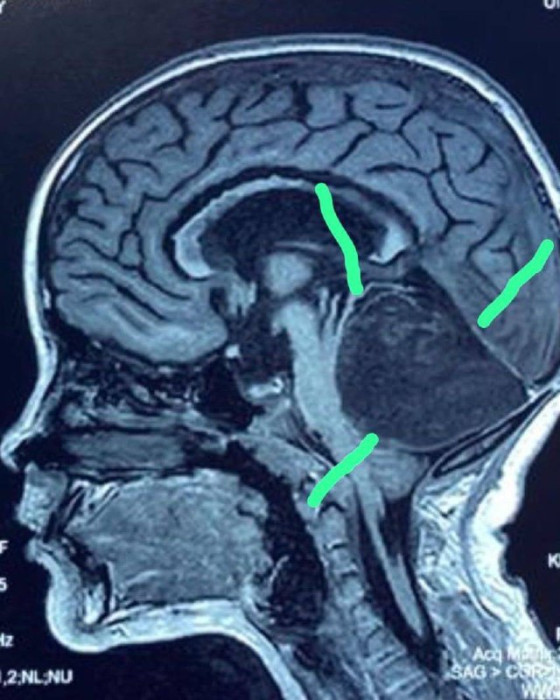

Маалымдалгандай, Жалал-Абад облусунун 8 жаштагы тургунуна баш мээнин 4-карынчасынын түбүндө чоң шишик (тератома) бар деген диагноз коюлган.

"Мээнин 4-карынчасынын түбүндөгү шишикти - тератоманы алып салуу операциясы ийгиликтүү өттү. Тератоманын ичинде бир тутам чач болгон, ал болжол менен бала төрөлгөндөн тартып ооруканага кайрылганга чейин өсүп келген", - деп айтылат маалыматта.

Операцияга Улуттук илимдер академиясынын академиги, профессор Миталип Мамытов жана кафедра башчысы Бакыт Карачев баштаган нейрохирургия бөлүмүнүн дарыгерлери катышкан.